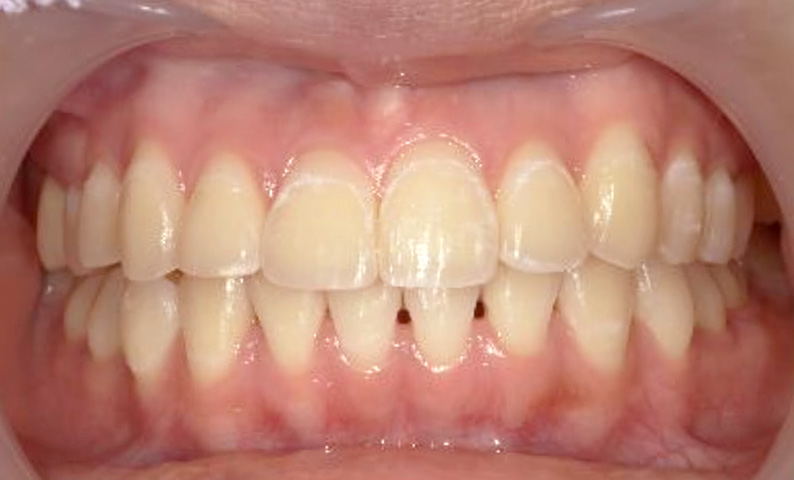

症例_005 上下顎の部分矯正

治療期間:11ヶ月金額:54万円+税女性前歯のガタガタ捻転歯

| Before | After |

|---|---|

|